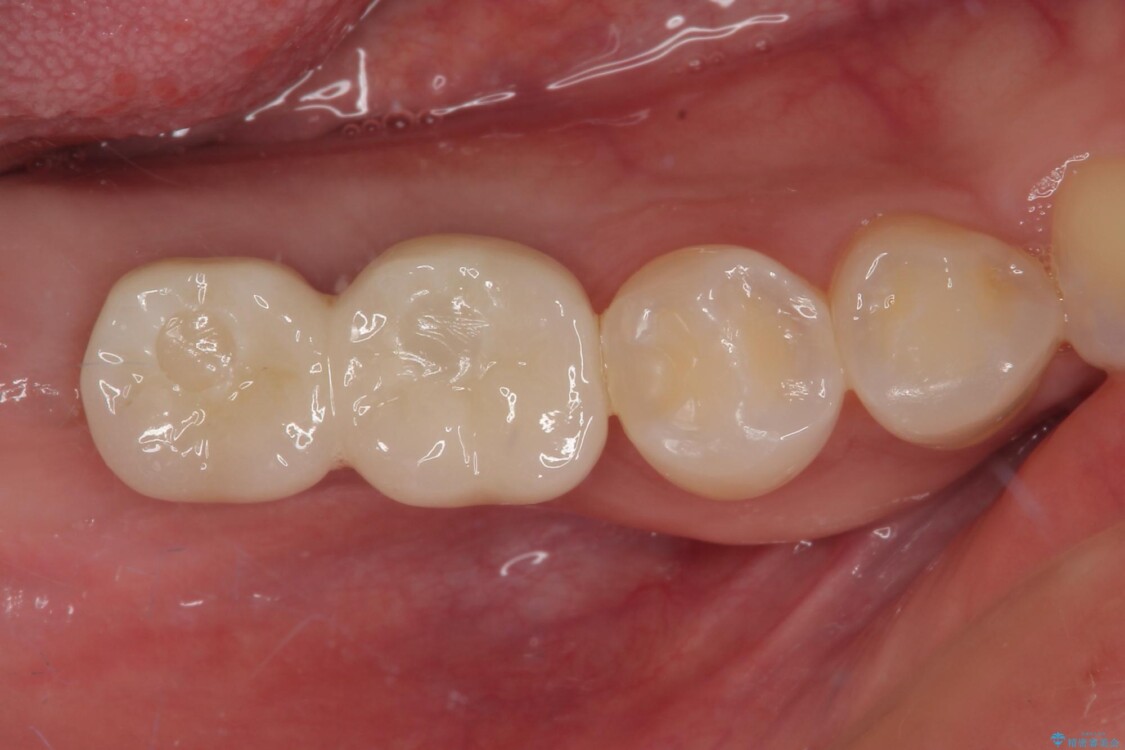

スペースが整った段階で、右下の第一大臼歯と第二大臼歯にインプラントを埋入。

その後、挺出していた右上第一大臼歯と第二大臼歯に装着されていた銀歯についても、審美性と適合性の向上を目的に、オールセラミッククラウンにやり替えました。

これにより、より自然で美しい見た目と、高い精度の咬合が得られています。

• 挺出歯を圧下してスペースを確保!目立たない部分矯正で下顎大臼歯にインプラント治療を実現 治療後画像